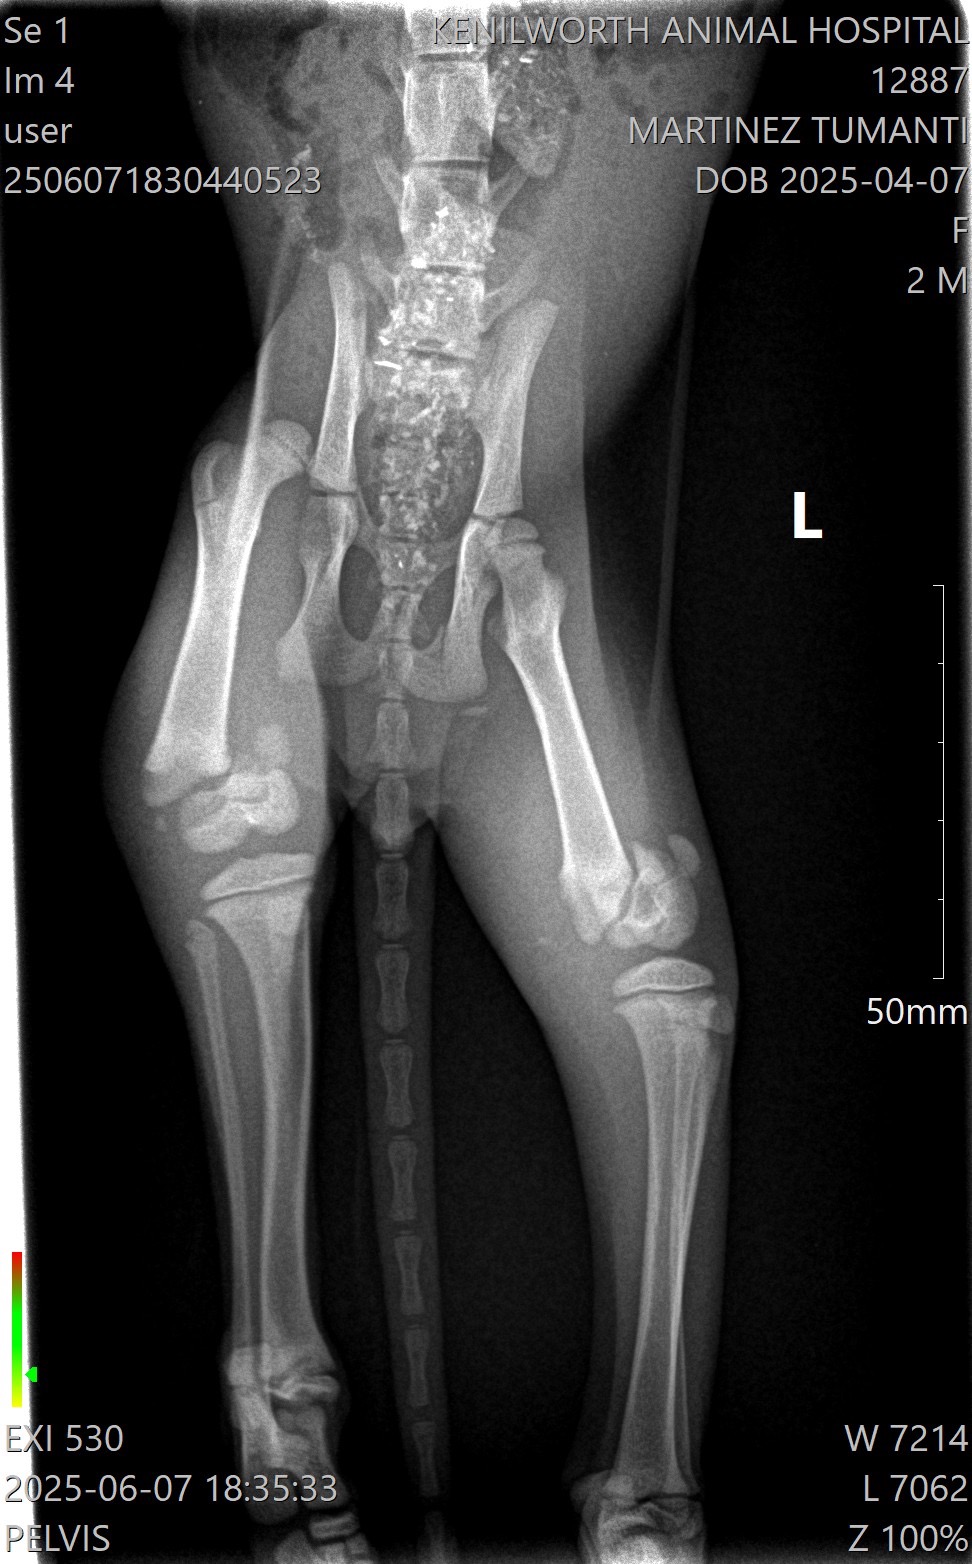

About a month ago, we found a tiny kitten on the side of the road. The kitten was crying and dragging his back legs behind him, barely able to move. We rushed to the emergency vet and they told us the kitten was about 8 weeks old and had a dislocated hip on his right side. We named him Skye, and committed to getting him everything he needs to heal.

After many vet consults and visits, an orthopedic specialist at Eclipse Veterinary Hospital confirmed the dislocated hip and also found bilateral distal fractures in both of his hind legs. He will need surgical repair of the fractures, follow-up care, X-rays and pain management.